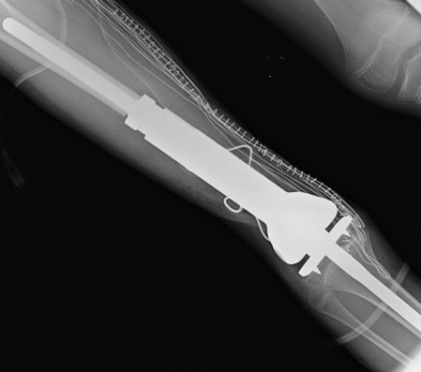

Il Codacons ha diffidato la Regione Puglia e tutte le Asl a contattarli immediatamente per procedere alla verifica ed alle procedure di controllo sanitario, al fine di accertare se sia necessario o meno procedere con urgenza alla sostituzione degli impianti. La protesi, a volte impiantata anche senza il diretto coinvolgimento dei pazienti, nel 2010 è stata ‘richiamata’ dalla ditta costruttrice poiché, dagli accertamenti effettuati dalla Johnson & Jonhson, è emerso che si possono produrre scollamenti delle componenti, sacche di liquido, dislocazione, sensibilizzazione al metallo, dolore e soprattutto, emissioni di ioni cobalto che interagendo con i tessuti molli possono produrre l’insorgenza di patologie cancerogene.